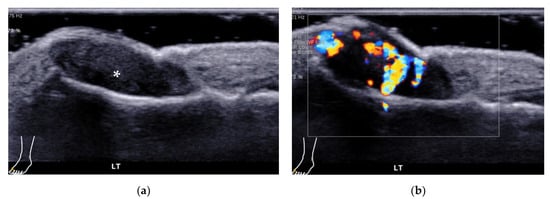

4.2.3. Intermetatarsal Bursitis

- Endo, Y.; Koga, T.; Eguchi, M.; Okamoto, M.; Tsuji, S.; Takatani, A.; Shimizu, T.; Sumiyoshi, R.; Igawa, T.; Kawashiri, S.Y.; et al. Utility of power Doppler ultrasonography for detecting forefoot bursae in early rheumatoid arthritis: A case report. Medicine 2018, 97, e13295. [Google Scholar] [CrossRef]